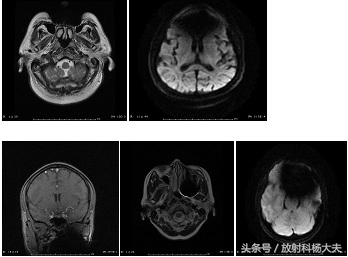

正常颅脑扫描图像